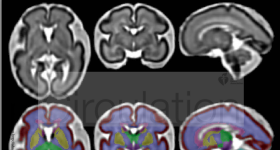

背景:神經(jīng)發(fā)育障礙在先天性心臟病(CHD)患兒中很常見,但產(chǎn)后變量?jī)H能解釋預(yù)后中30%的差異。為了探討神經(jīng)發(fā)育障礙...